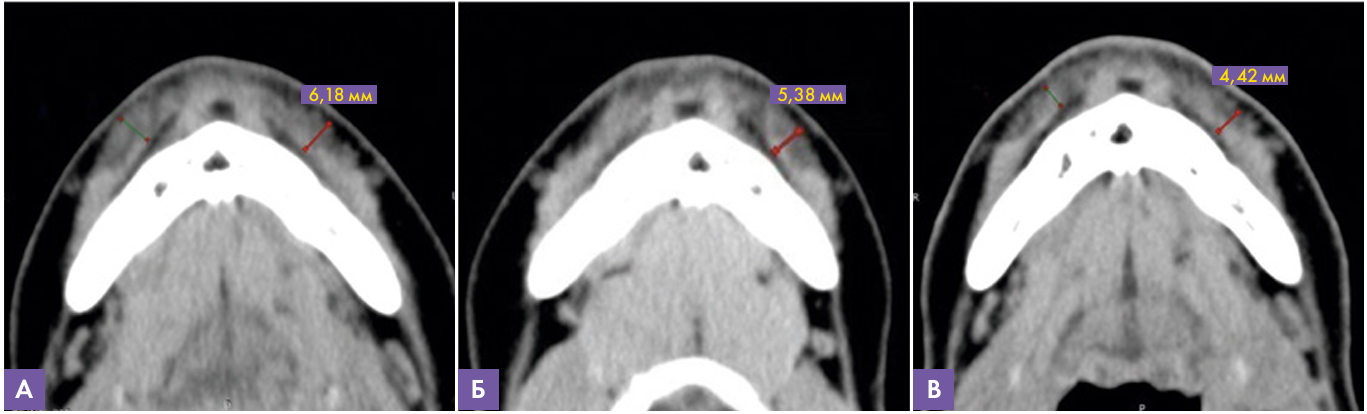

На аксиальных срезах подбородочной области (рис.10) в мягких тканях губно-краевой области справа и слева визуализируется наличие имплантата на основе гиалуроновой кислоты, интимно прилежащего к мышце, опускающей нижнюю губу (толщина которой 2 мм по данным МСКТ исследования до инъецирования). При динамическом исследования через 12 месяцев отмечается уменьшение толщины слоя, включающего мышцу и филлер, с 6,2 мм до 4,42 мм. Так же следует отметить постепенное формирование негомогенной структуры препарата за счет участков пониженной плотности. Данных за наличие инфильтративных изменений, признаков миграции и инкапсулирования препарата не выявлено.

Рисунок 10. МСКТ сканы подбородочной области слева, аксиальная проекция

А – через 5 месяцев, толщина имплантата 6,18 мм

В – через 9месяцев, толщина имплантата 5,38 мм

С – через 12 месяцев, толщина имплантата 4,42 мм